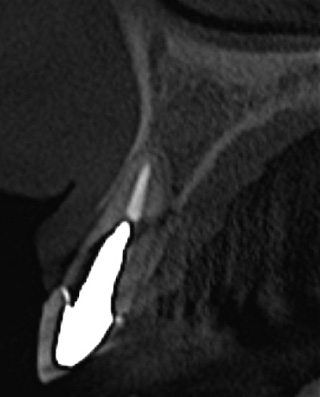

Single-tooth replacement in the esthetic zone has been one of the most common indications for dental implant placement. Compromised teeth are removed using atraumatic principles and immediately replaced by an implant-supported provisional restoration, with excellent esthetic, biological, and functional results.

However, in cases of compromised sites with bone loss/gingival recessions, the clinical scenario presents a different dilemma. Until now, all developed surgical recommendations required long-term treatment with possible undesirable complications in the tissue architecture.

The Immediate Dentoalveolar Restoration (IDR) is a surgical and prosthetical technique established to broaden indications for immediate loading on individual teeth. In this way, tissue losses with varied extensions are reconstructed in the same surgical session of implant placement and provisional crown installation, reducing the number of interventions and keeping predictability on esthetic aspects. The IDR protocol was developed more than 12 years ago from the need to minimize the treatment time

It is presented several cases, which showed one or more compromised socket walls of the tooth involved, with or without changes of the gingival margin, some with more than 12 years of clinical, radiographic and CT scan follow-up.